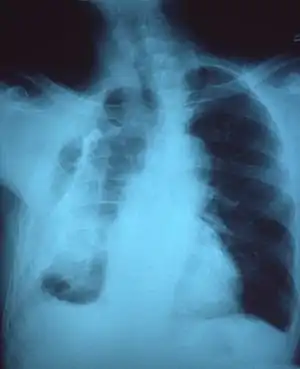

Extensive left-sided fibrothorax

Chest radiograph displaying inhomogeneous opacification of the left half of the chest that is fibrothorax

A fibrothorax can typically be diagnosed by taking an appropriate medical history in combination with the use of appropriate imaging techniques such as a plain chest X-ray or CT scan.[3] These imaging techniques can detect fibrothorax and pleural thickening that surround the lungs.[7] The presence of a thickened peel with or without calcification are common features of fibrothorax when imaged.[3] CT scans can more readily differentiate whether pleural thickening is due to extra fat deposition or true pleural thickening than X-rays.[3]

If a fibrothorax is severe, the thickening may restrict the lung on the affected side causing a loss of lung volume.[7] Additionally, the mediastinum may be physically shifted toward the affected side.[3] A reduction in the size of one side of the chest (hemithorax) on an X-ray or CT scan of the chest suggests chronic scarring.[6] Signs of the underlying disease causing the fibrothorax are also occasionally seen on the X-ray.[6] A CT scan may show features similar to those seen on a plain X-ray.[7] Lung function testing typically demonstrates findings consistent with restrictive lung disease.[6]